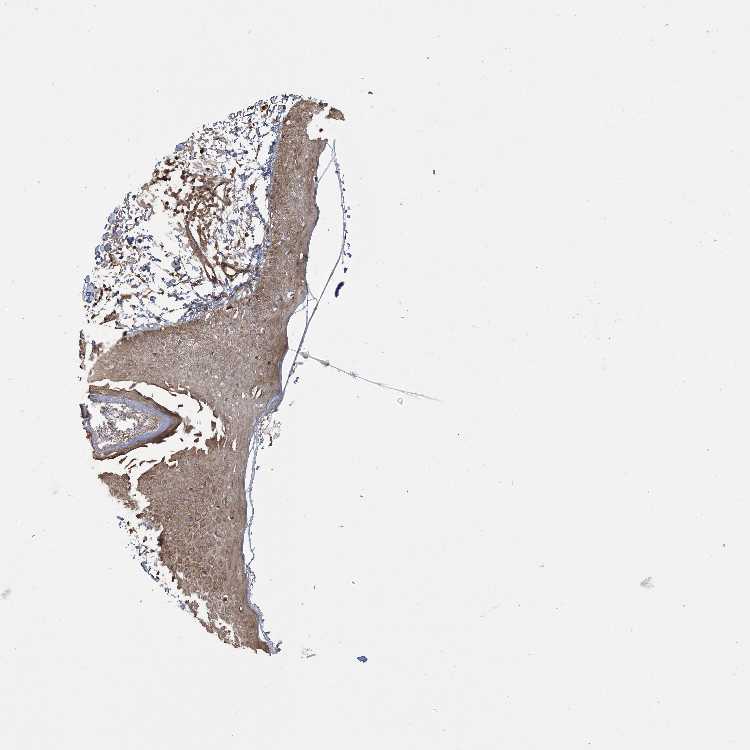

SKIN 2 - Antibody stainingi

Antibody staining in the annotated cell types in the current human tissue is reported as not detected, low, medium, or high, based on conventional immunohistochemistry profiling in selected tissues. This score is based on the combination of the staining intensity and fraction of stained cells.

Each image is clickable and will lead to virtual microscopy that enables deeper exploration of all samples and also displays staining intensity scores, fraction scores and subcellular localization as well as patient and tissue information for each sample.

Antibody HPA035027Antibody HPA035028

Epidermal cells LowMedium